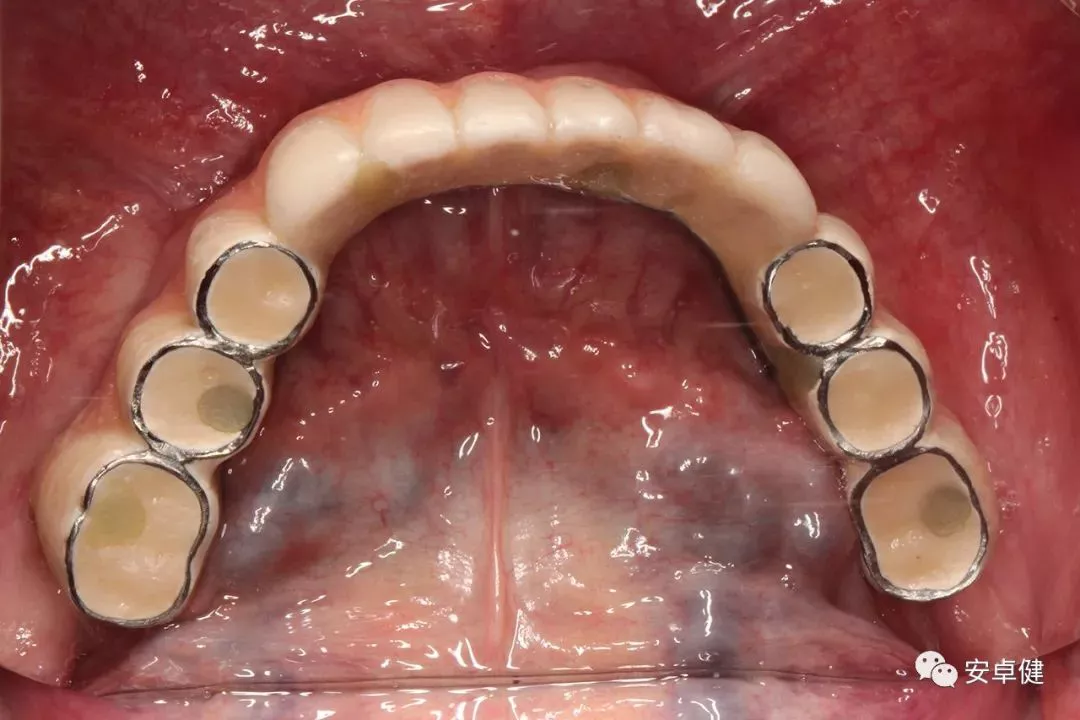

最终修复体合面照

戴最终修复体合面观

▷ 永久修复

• 于口内试戴原厂纯钛切削一体式桥架,并检查前牙排蜡外形及后牙咬合关系;

• 聚合瓷烤塑制作最终修复体;

• 为减少牙面磨耗,于后牙区制作360度防裂纯钛金属带;

• 试戴满意后,二级螺丝加力至15N;

• 特氟龙封闭螺丝孔,光固化复合树脂封闭上方螺丝通道,完成最终固定式种植义齿修复;

• 修复体外形能够正确恢复面下1/3高度及侧貌;

• 患者可获得较为稳定的咬合关系,并满足其咀嚼功能的需求;

• 患者42、46部位牙龈退缩,缺乏足够的角化龈,为方便后期清洁维护,选择穿龈较高的龈上肩台;

• 口内观察,修复体边缘金属基台颜色暴露,但由于其处于下颌后牙非微笑暴露区,故对临床整体美观效果的影响在患者可接受范围内。